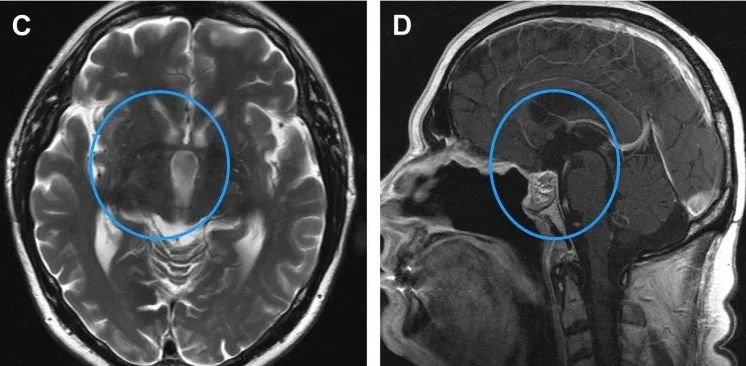

术后,Klaus曾经历短暂的意识模糊期,然而他的神志和认知功能迅速恢复,体重也保持稳定。术后两年内,未见肿瘤复发迹象。MRI检查结果显示,他的水肿已完全消退,且鼻中隔皮瓣成功重建了颅底。